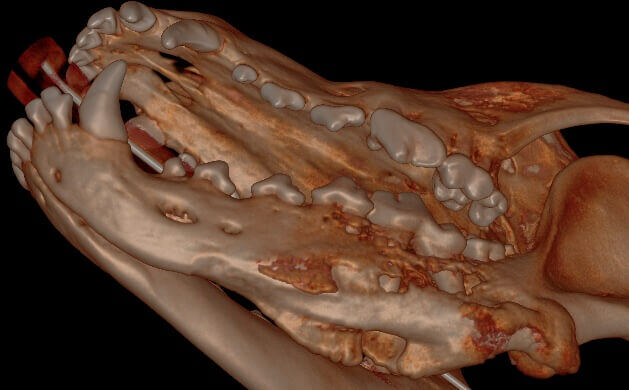

.jpg?width=629&height=390&name=3D%20Hard%20Tissue%20Overview%20(left%20mandible).jpg)

Below: 3D Hard Tissue Lingual View (left mandible)